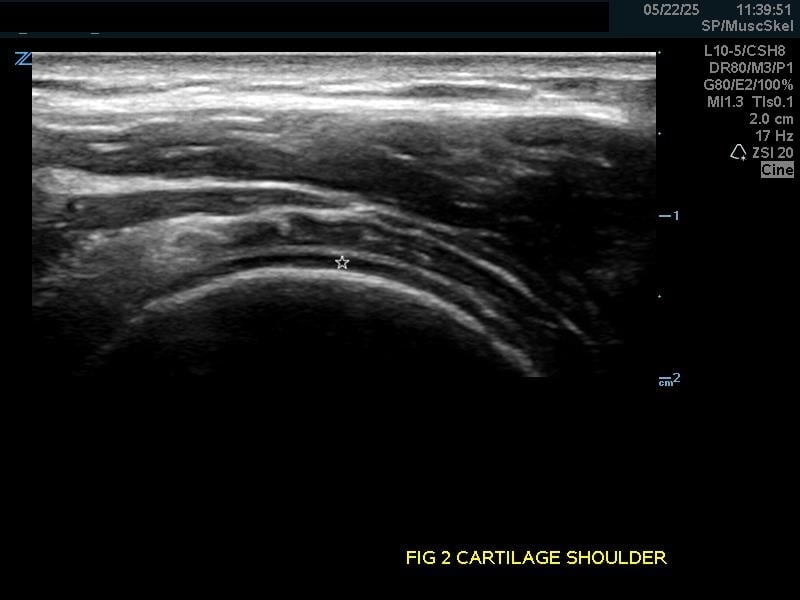

Hyaline Articular Cartilage: Appears as a thin very hypoechoic rim over a hyperechoic bony cortex. It is so hypoechoic it may be confused with fluid.

Figure 2.

(A) Hyaline articular cartilage (star) of the shoulder and (B) knee.